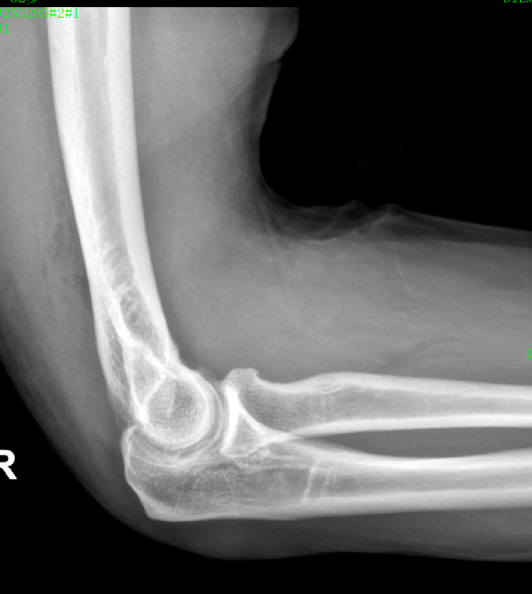

近日,一位52岁的男性患者,因右肘疼痛伴活动受限2周余来pilipili 就诊。经检查,确诊为肘关节骨性关节炎伴游离体。患者于入院第二天在气管插管麻醉下行右肘关节镜探查+滑膜切除+游离体取出术。术后症状明显缓解,疼痛减轻,关节活动范围改善,现已成功出院。

患者鹰嘴骨质增生;前侧关节腔游离体形成

术后CT、DR提示游离体取出